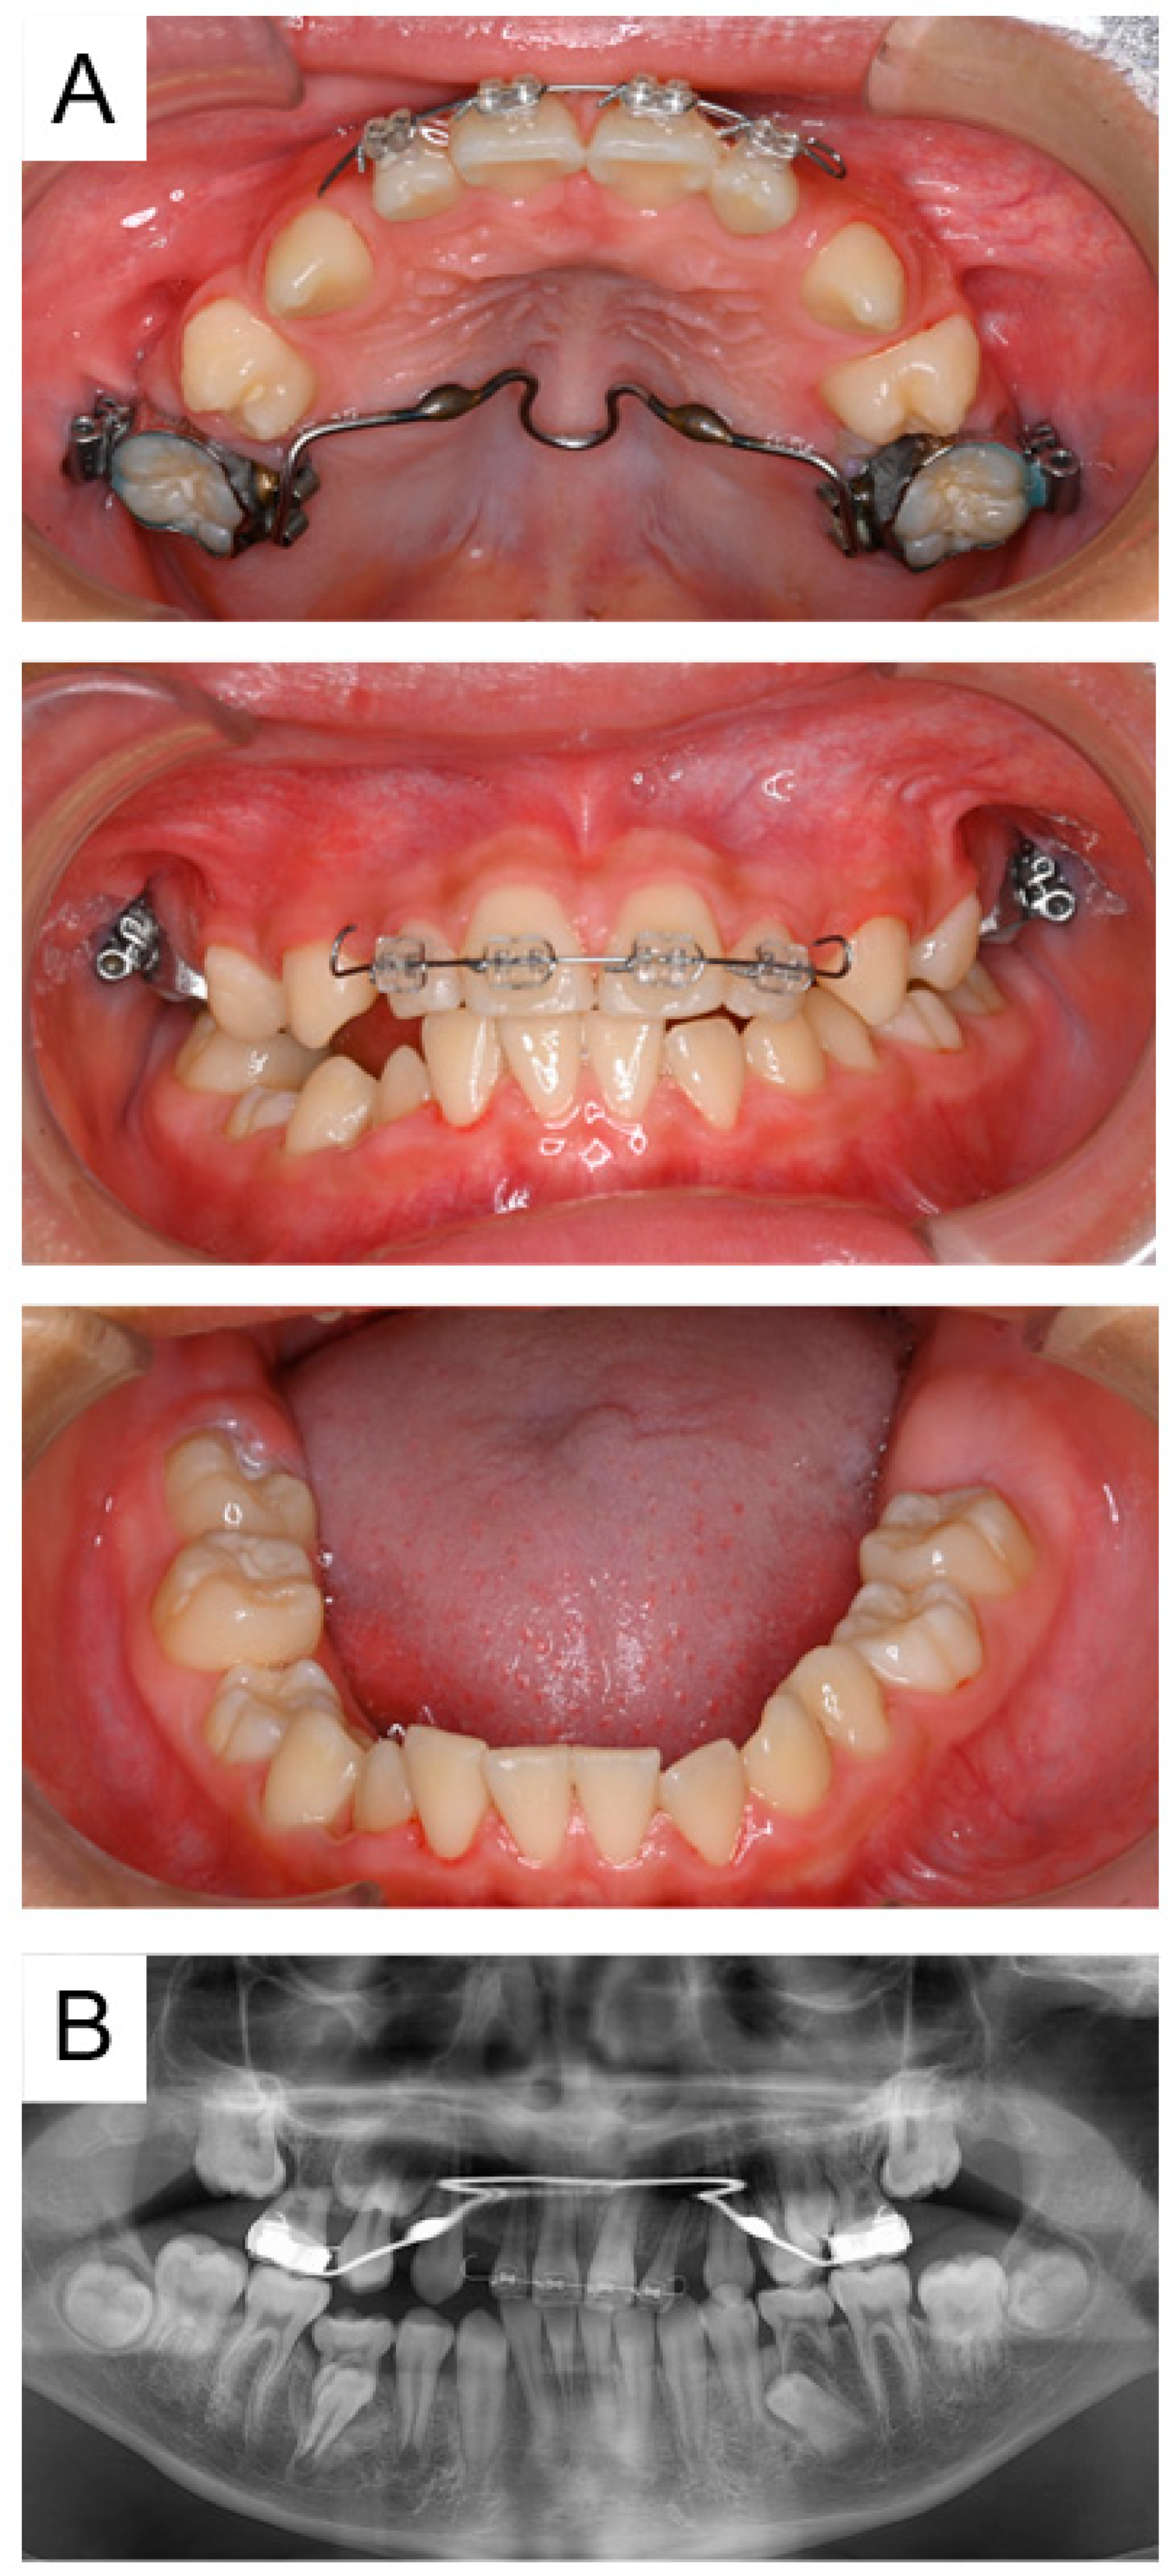

2.1. Case 1

2.2. Case 2